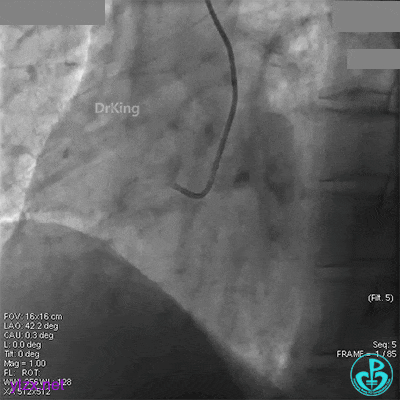

回旋支中段植入2.75×33mm支架后造影,前向血流中断,患者开始出现胸痛。

闭塞段植入2.75×33mm支架后前向血流中断,要排除无复流和支架两端夹层。

近端串联植入3.5×23mm支架后造影,前向血流没有恢复,患者感胸痛明显。

经刺破球囊冠脉内推注硝普钠后血流恢复2级,远端分支血管没有充分显影。